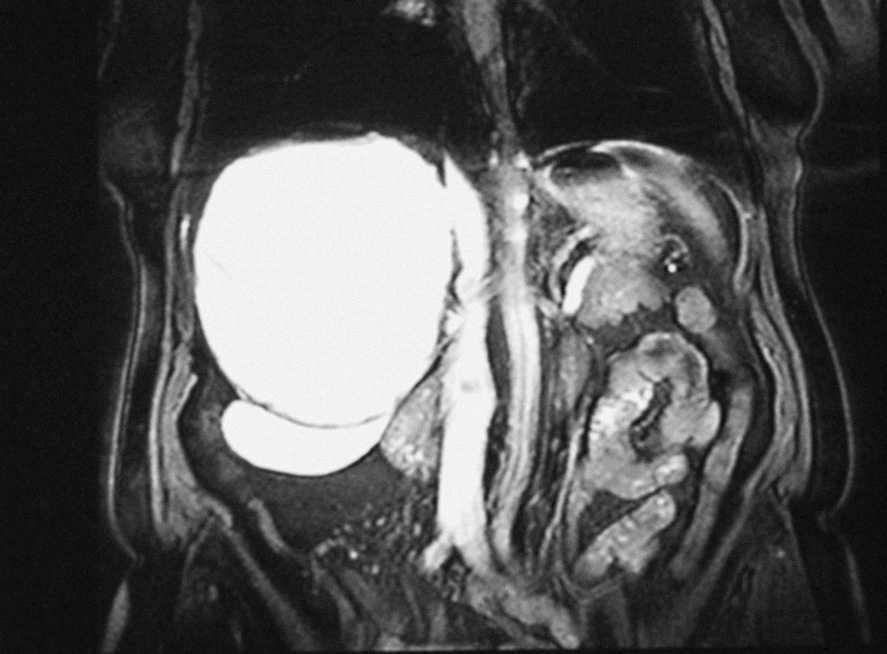

Mujer de 67 años sin antecedentes de interés, que presenta tos irritativa y a la que se detecta una masa hepática en la tomografía computarizada torácica realizada para descartar patología pulmonar. La exploración clínica y la analítica resultan anodinas. La resonancia magnética abdominal demuestra una masa quística hepática bien delimitada, de 15 x 11 x 12 cm, que ocupa todo el lóbulo hepático derecho (fig. 1), con contenido homogéneo, sugestiva de quiste hidatídico, y una hipertrofia compensadora marcada de los segmentos II y III, que miden 20 x 12 x 7 cm (fig. 2 y 3). Se practicó quistoperiquistectomía subtotal abierta. Al año de seguimiento se encuentra asintomática.

Fig. 1.